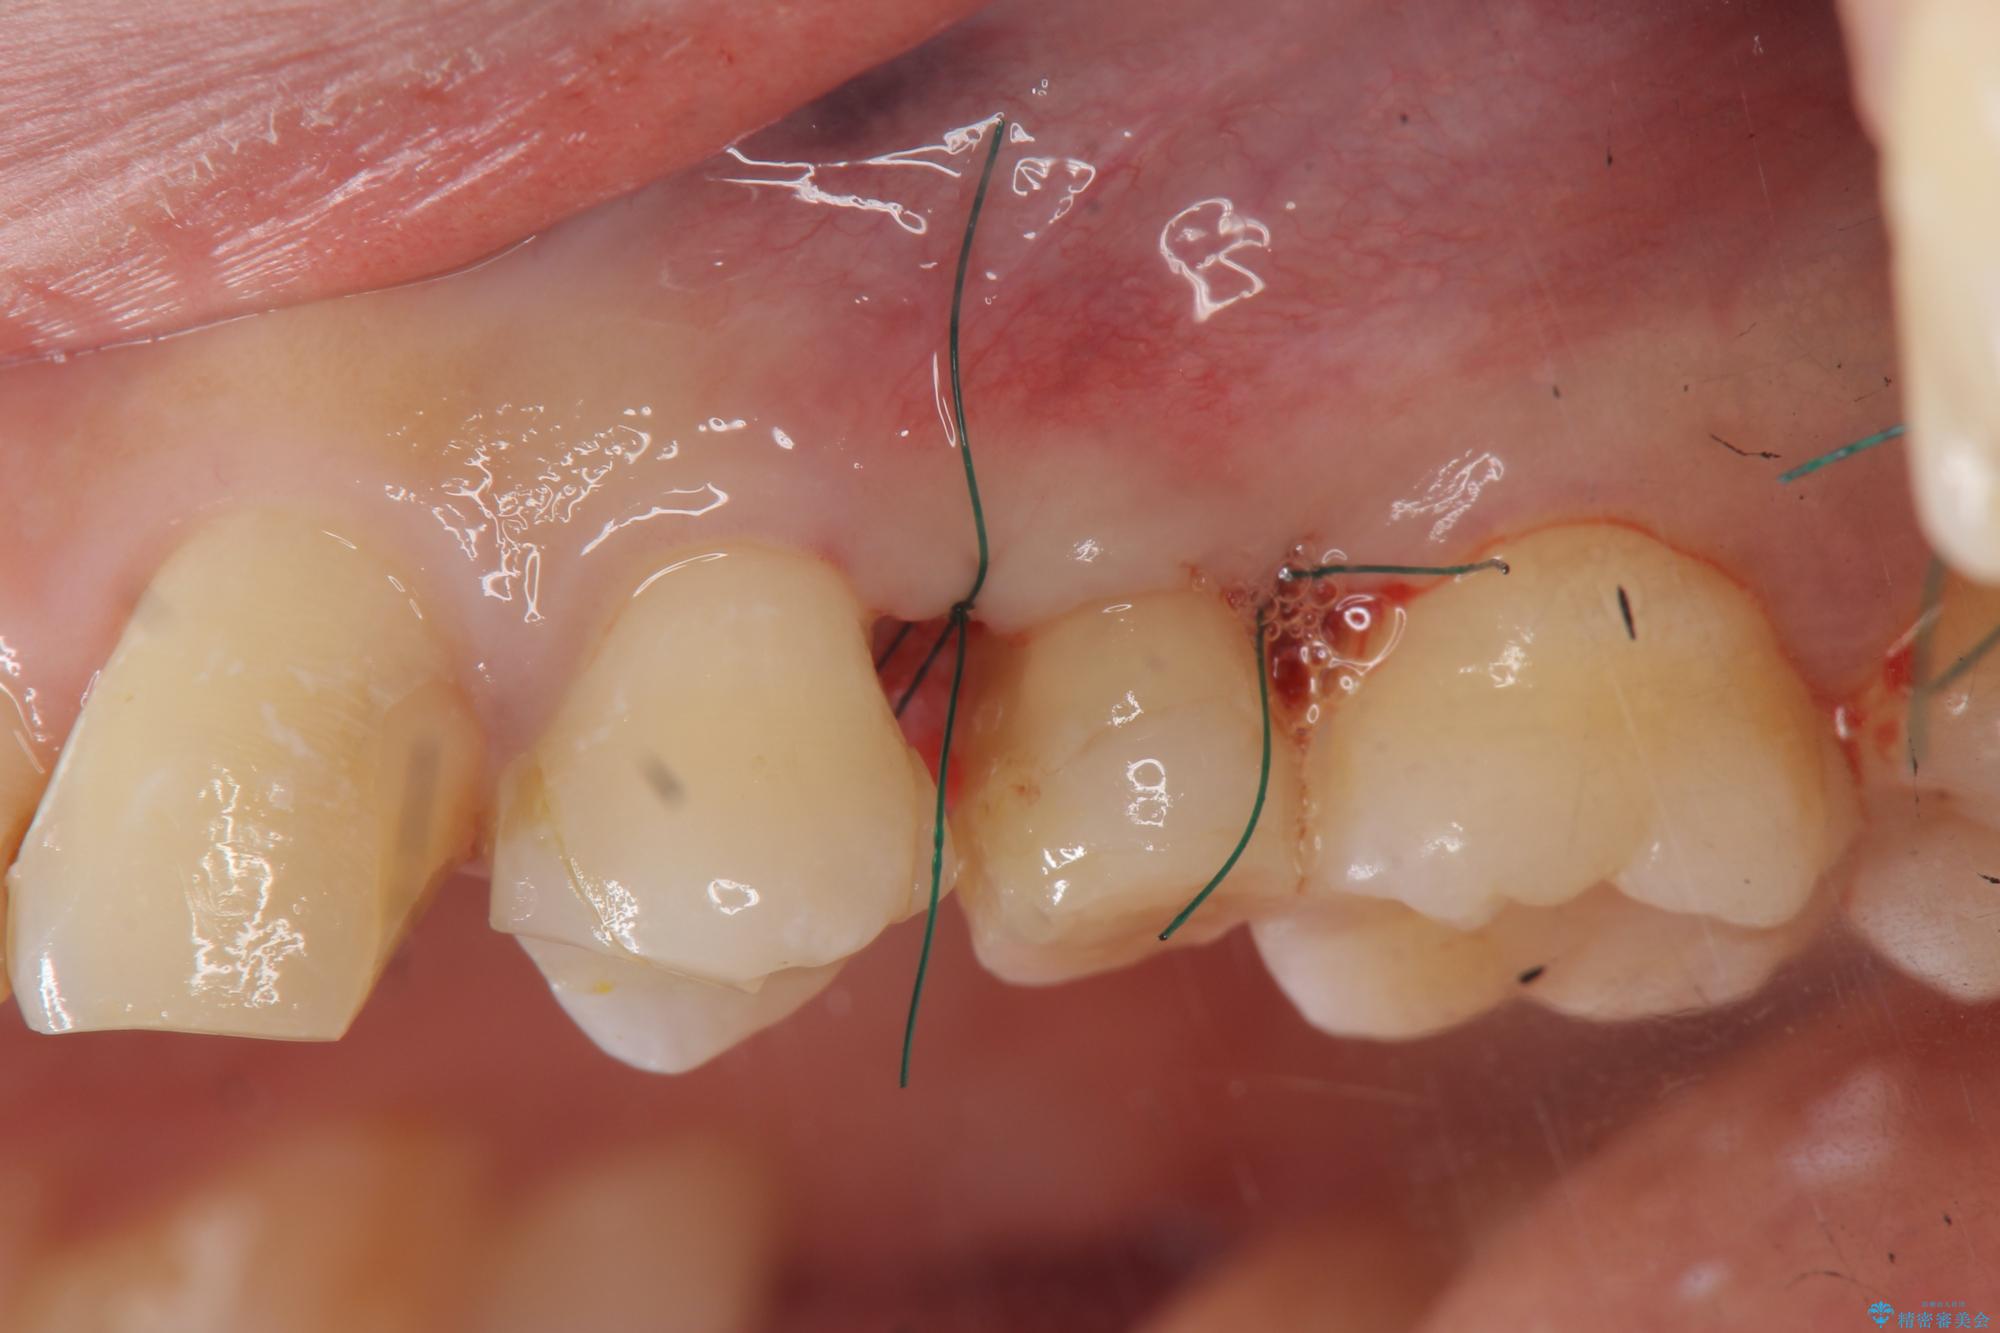

- 歯ぐきの腫れや、歯の内部が黒く見えることからの虫歯の治療を求めて来院されました。

虫歯が大きかったことから、神経の温存はできたものの歯ぐきよりも深い虫歯の問題を解決するため部分矯正治療を併用したセラミック治療を行うこととしました。

当初、歯ぐきよりも深い虫歯のぞんざいや、歯のポジションに問題がありましたがマルチブラケットを用いた部分矯正を行うことで適切な位置へと歯を移動させ、歯周環境を整えたセラミック治療を行うことができました。